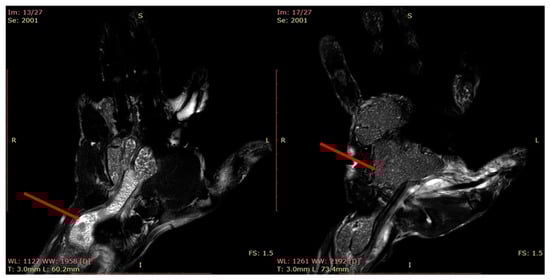

| 6 | Idiopathic Tenosynovitis with “rice bodies” |

| Well-defined tumor mass with both solid and liquid content (mixed) | Well-defined lobular, multiloculated tumor formation, heterogeneous with hyposignal in T1 and iso/hypersignal in T2. Numerous small hyposignal areas in T2; T1-weighted sequence showing a mass with low signal intensity surrounding the tendons |